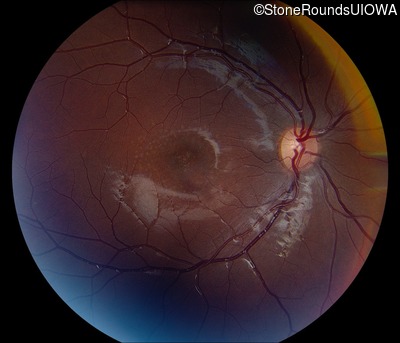

AR Stargardt Disease (IIA)

AR Stargardt Disease (IIA)

This 11 year old female first had difficulty seeing the blackboard at age 8. Later, she developed some photophobia.

Diagnosis & molecular findings

| Disease | Gene | Allele 1 variant(s) | Allele 2 variant(s) | Inheritance mode |

|---|---|---|---|---|

| AR Stargardt Disease | ABCA4 | Gly1961Glu GGA>GAA, Arg212Cys CGC>TGC | Gly1961Glu GGA>GAA, Arg212Cys CGC>TGC | AR |